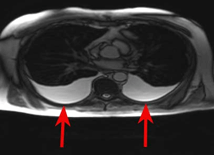

D1.  D2.

D2.

D3.

Figure D. In image D1, the TE7 Ultrasound machine is looking at the inferior vena cava (IVC). Image D2 shows the lung with ultrasound and D3 shows a cardiac assessment with smart measurements to check heart function. Images courtesy of Mindray Medical International.